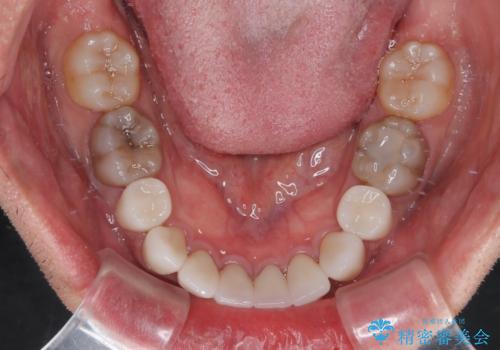

- 口元の突出感を改善するための抜歯矯正を終えた患者様ですが、幼少期からの変色した歯をセラミッククラウンにて自然な色合いに変えていくこととしました。

口を開けたときに目につく範囲を希望されたため上下ともに8本ずつをオールセラミッククラウンによる補綴治療を行うこととしました。

近年では大変珍しいですが、胎児あるいは乳幼児期の抗生物質の影響で永久歯が変色してしまうことがあります。

ホワイトニングでの改善は期待できないため、オールセラミッククラウンによる補綴治療が必要となります。